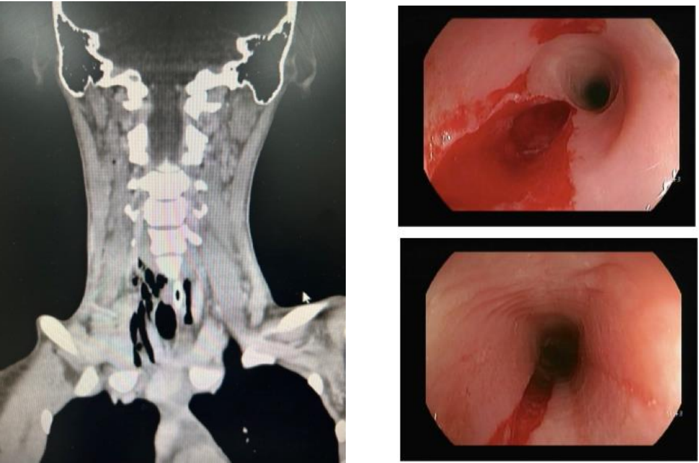

Paciente feminina, 21 anos, após confraternização de fim de ano, apresenta sensação de alimento preso na garganta, odinofagia, sialorréia, regurgitação e náuseas (sem vômito). Compareceu ao prontosocorro onde realizou exames laboratoriais e de imagem.

Exames laboratoriais: Hemoglobina 11,1 g/dL, Leucócitos 6.730/mm³, Plaquetas 151.000/mm³, PCR 1,23 mg/L (VR<1,0), Creatinina 0,65 mg/dL, Ureia 24 mg/dL, Sódio 139 mEq/L, Potássio 4,0 mEq/L, Bilirrubina Total 0,23 mg/dL, Amilase 62 U/L, INR1,14.

Endoscopia laudava esôfago com mucosa conservada até 20cm da ADS com laceração profunda onde encontra-se corpo estranho impactado. Retirado com auxílio de Roth Net sem intercorrências. Realizada também tomografia computadorizada de pescoço. Vide imagens abaixo.

Qual deve ser a conduta imediata?